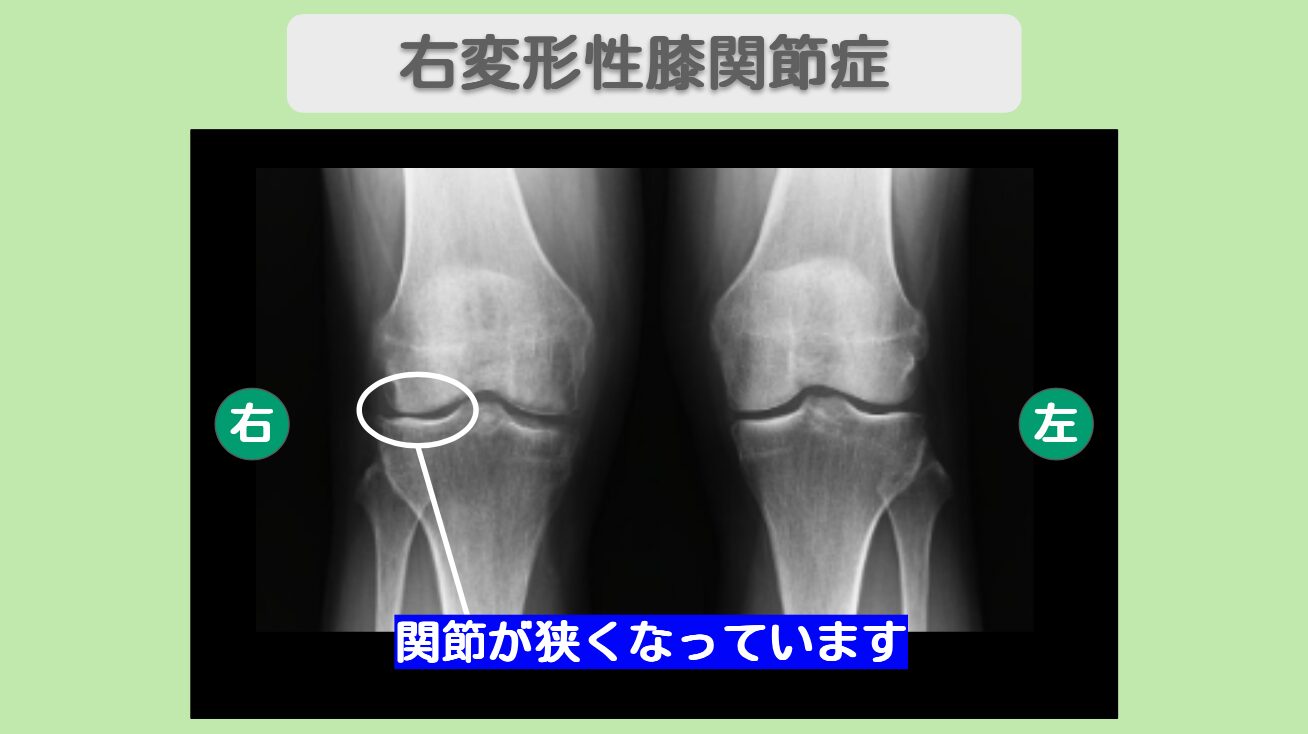

痛み大幅改善で関節鏡手術を回避! 右外側半月板損傷・右変形性膝関節症 60代女性

- 右膝外側半月板損傷、変形性関節症初期と診断

MRI・レントゲン所見

MRIにて半月板後節の損傷を認めます。